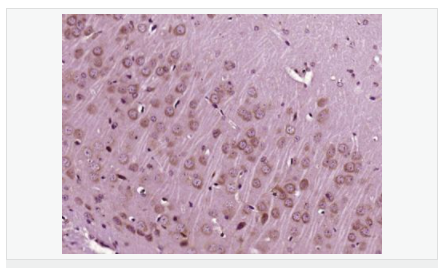

產(chǎn)品應(yīng)用WB=1:500-2000 ELISA=1:5000-10000 IP=1:20-100 IHC-P=1:100-500 IHC-F=1:100-500 IF=1:100-500 (石蠟切片需做抗原修復(fù))

image.png